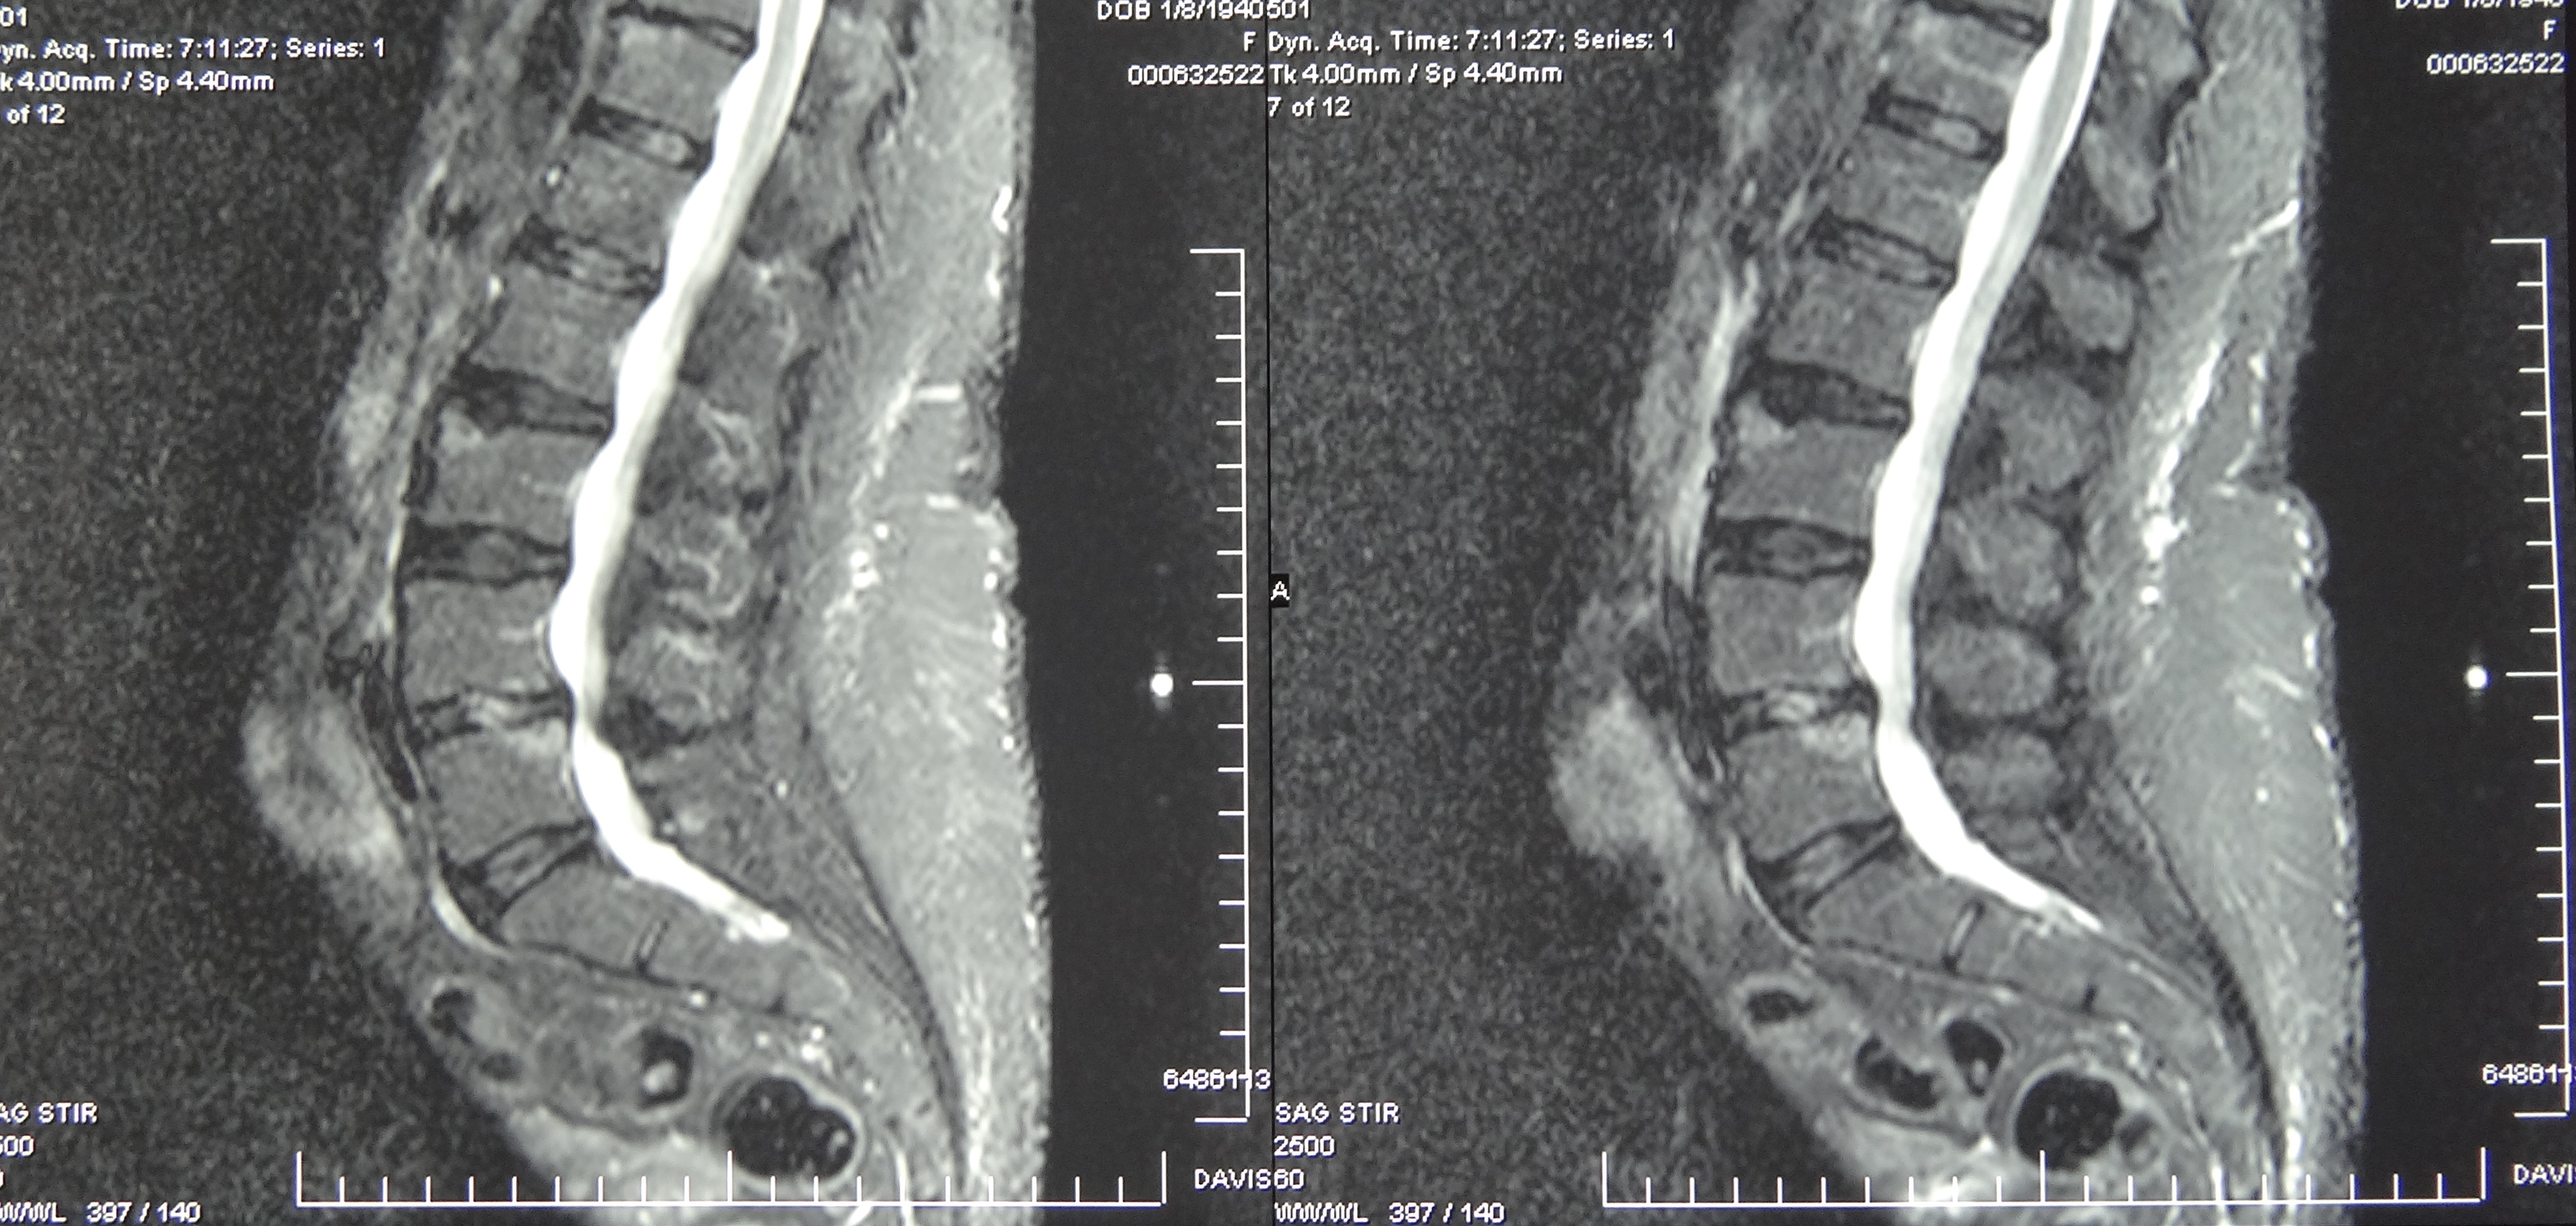

March 2019 MRI

IMPRESSION:

- Complete rupture proximal third anterior cruciate ligament with pivot shift

pattern of bone injuries lateral compartment and contrecoup bone contusion

medial tibial plateau. Joint hemarthrosis. - Complex tear lateral meniscus with inferiorly flipped flap tear extending

into the popliteal hiatus. - Complex tear medial meniscus with outwardly extruded tears of the posterior

horn and body. - Low-grade sprains medial collateral ligament and medial posterior oblique

ligament. - Low-grade sprains fibular collateral ligament and anterolateral ligament.

Intermediate to high-grade sprain popliteofibular ligament and arcuate ligament. - Grade 1 strains vastus lateralis, short head biceps, sartorius, soleus,

popliteus and anterior compartment muscles.